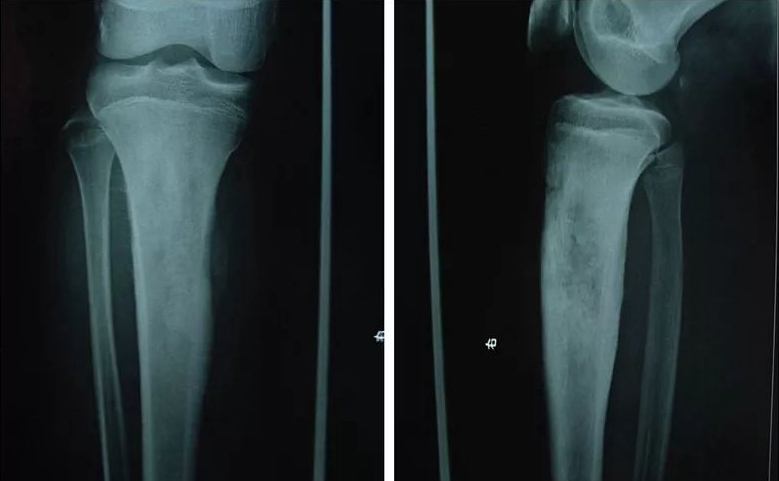

CT掃描可提供更豐富的影像信息。CT用于明確髓內(nèi)和軟組織腫塊范圍較X線平片敏感,在髓腔內(nèi)CT值的增高一般提示已有腫瘤的浸潤,并能及早發(fā)現(xiàn)髓腔內(nèi)跳躍灶(圖2)。CT對骨肉瘤的瘤骨顯示優(yōu)于X線平片和MRI檢查,這是由于瘤骨周邊部分的骨化弱于中央部分,CT掃描可敏感地分辨較弱成骨的周邊部分,MRI常不易區(qū)分信號相近的弱成骨區(qū)和未成骨區(qū)。肺部CT掃描是確認(rèn)有無肺轉(zhuǎn)移灶的好方法。

圖2. 典型的骨肉瘤CT表現(xiàn)